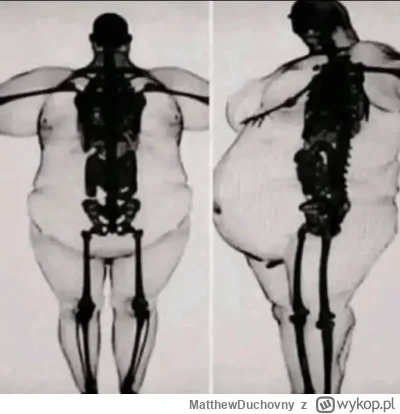

Kolejny lek na leczenie otyłości. Jest zgoda władz

Amerykańskie organy regulacyjne zatwierdziły specyfik Zepbound firmy Eli Lilly do leczenia otyłości. To zwycięstwo producenta leków